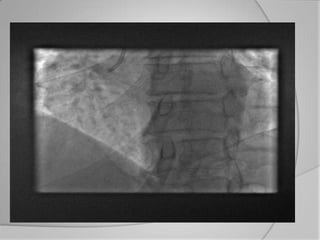

Phase hospitalière

   les patients avec le plus haut risque (infarctus avec surélévation ST,

choc cardiogène) sont acheminés dans le cas idéal directement en

salle de cathétérisme.

   Les autres patients sont admis aux services d’urgences ou des

soins intensifs pour un premier traitement préliminaire, avec un

monitoring du rythme cardiaque (et éventuellement de l’élévation

du segment ST), des premières investigations et une stratification

de risque.